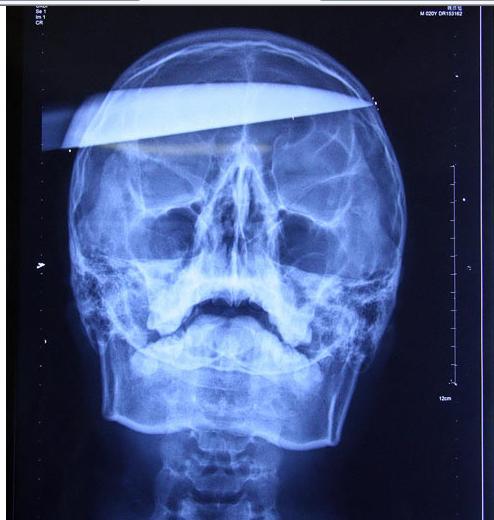

تصویر: چاقوی 25 سانتیمتری در جمجمه

پسری با چاقوی 25 سانتیمتری در جمجمه اش وارد بیمارستان شد و باعث تعجب پزشکان در چین شد.